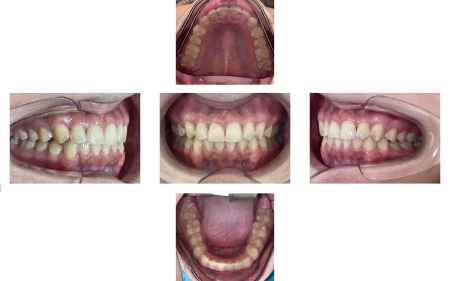

噛み合わせの位置が改善され、歯並びもきれいになりました。

患者様には「すごくきれいになった」と大変ご満足いただきました。

現在は、後戻り防止のための装置「保定装置」を使用していただき、定期的に経過を確認しています。